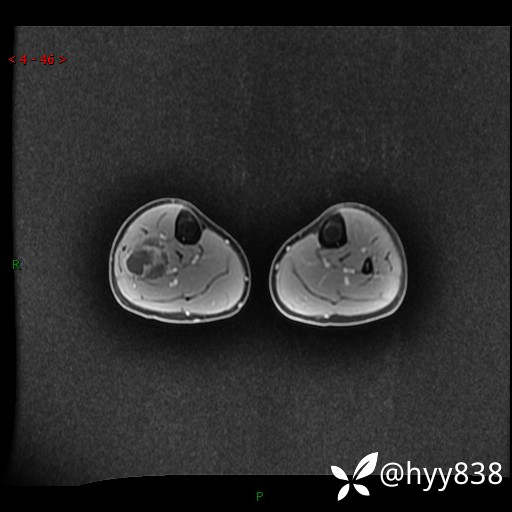

MRI 增强(cor+sag+axi)